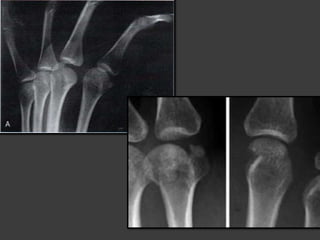

Fractura de 1er

Metacarpiano

Clasificacion de MacNeal

Fractura de Bennett

Fractura de Rolando

 Fractura en V, Y o T de la base del 1er

metacarpiano cuya reduccion anatomica

es dificil y lleva a la artrosis

trapeciometacarpiana